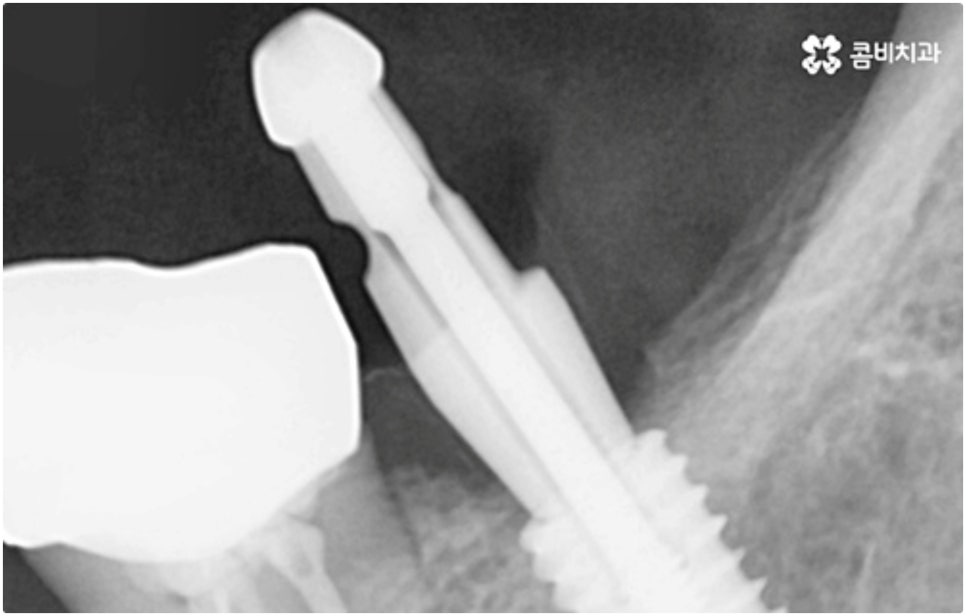

임플란트 시술이 환자분들의 잇몸뼈에 직접 고정을 시키는 방법인 만큼 개개인의 치주 상태, 구강 내부 구조 등을 면밀하게 살펴보고 치료 계획을 세워야 하며 그 밖에도 치아가 빠진 지 얼마의 시간이 흘렀는지, 장기적으로 복용 중인 약이 있는지 등 영향을 줄 수 있는 모든 관련 상황을 종합적으로 고려하여 환자분들에게 딱 맞는 어금니임플란트 시술을 무리하지 않게 진행하는 것이 중요한 체크 포인트라고 할 수 있는데요. 그렇기 때문에 먼저 3D CT를 이용한 정밀한 검사를 통해 어떤 종류의 임플란트를 어떻게 진행할지 신중하게 검토해야 하며 또한 풍부한 노하우와 뛰어난 기술력을 갖추고 있는 의료진과 함께 충분한 사전 상담을 하실 필요가 있습니다.

식립 성공률 및 지속적인 안정성을 높이기 위해서는 초기 고정이 잘 이루어져야 하는데 만약에 식립 바탕이 되는 잇몸뼈의 상황이 좋지 않다면 이와 관련된 치료를 먼저 해 줘야 하는 거예요. 예를 들어 치주 질환이 심하다면 이를 깨끗하게 치료해 주는 것이 우선시 되어야 하고, 잇몸뼈의 높이나 밀도 등이 부족한 경우에는 뼈이식 과정을 통해 이를 먼저 보충해 줄 필요가 있어요. 또한 윗어금니가 빠진지 오랜 시간이 지나 이미 골흡수가 일어나고 상악동이 많이 내려와 있다면 상악동 거상술 및 뼈이식을 한 후 임플란트 식립을 진행해야 할 거예요.

이와 같이 상악의 경우 상악동과 비강저(콧구멍 바닥)까지의 거리 및 신경과 혈관분포, 하악의 경우 하치조 신경 및 하치조관과 이공까지의 거리, 주위 조직 등에 대한 면밀한 검진과 파악이 필요하기 때문에 임플란트 시술을 진행할 때 상하악골 및 주변 조직을 해부학적으로 자세히 체크할 수 있는 정밀 장비 및 담당 의료진의 숙련도가 굉장히 중요한 요소라고 할 수 있어요.